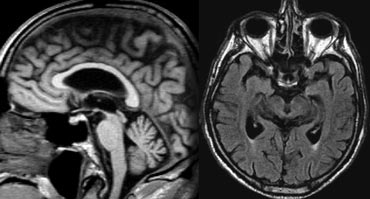

Vascular dementia, no medial temporal lobe atrophy. Vascular dementia, no medial temporal lobe atrophy.

In most patients with VaD there is diffuse white matter disease with large confluent lesions (Fazekas 3).

In some of these patients the ventricles may be dilated due to global atrophy and some will also have medial temporal lobe atrophy.

The images are of a patient who had VaD, but the medial temporal lobe was normal.

MTA in a patient with VaD MTA in a patient with VaD

On the left we see a patient who was diagnosed as having VaD.

White matter disease is seen as severe WMH (hypointense on T1) in the periventricular regions.

In addition to these vascular changes, there is also MTA.

Presumably this patient has both VaD and AD, a finding seen in many elderly patients.

These findings should be described separately as it may have therapeutic consequences.